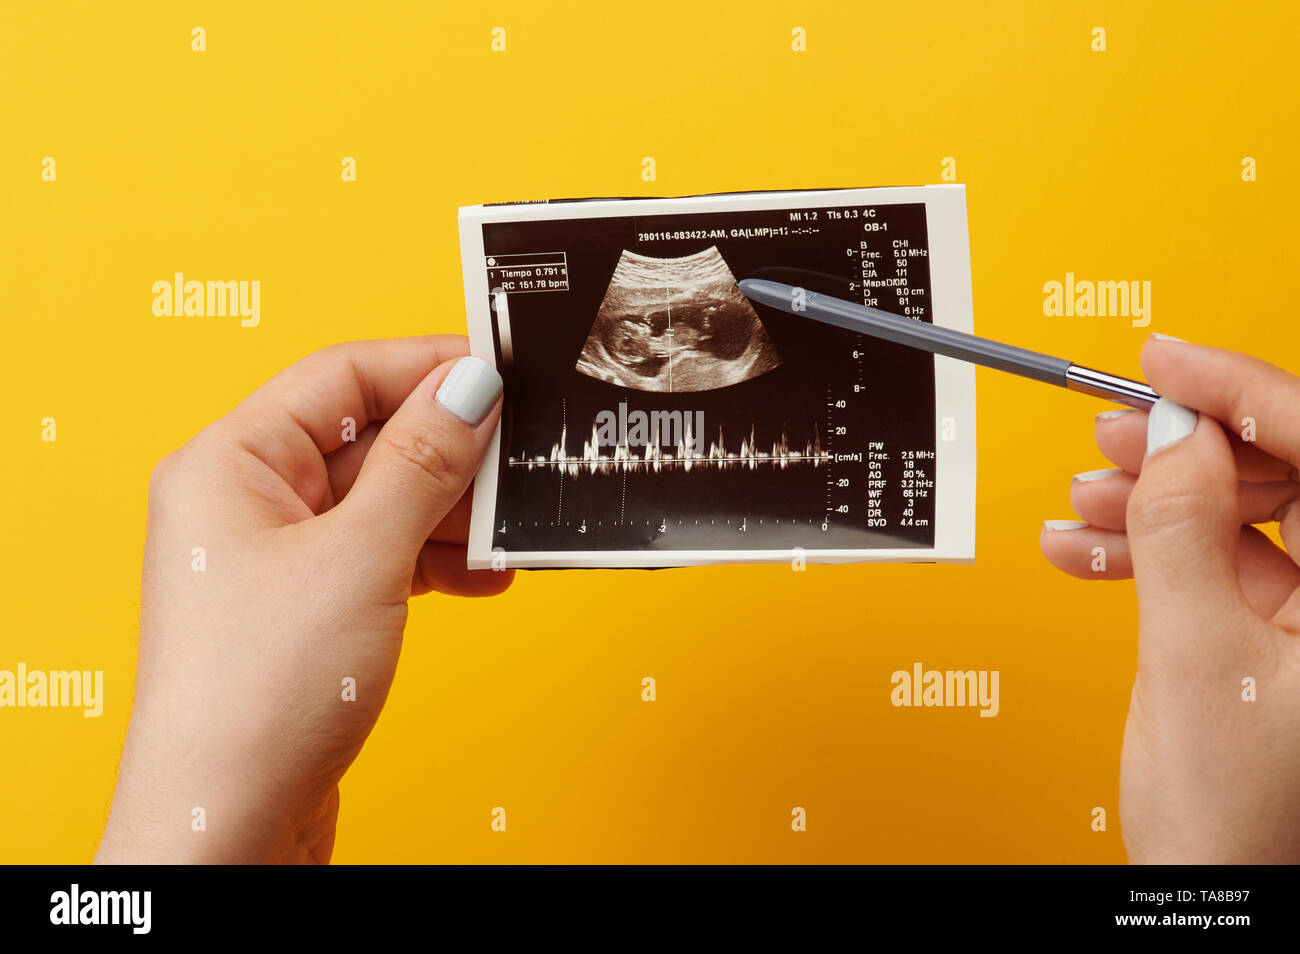

Browsing ultrasound photo. Checking scan of pregnant woman Stock Photohttps://www.alamy.com/image-license-details/?v=1https://www.alamy.com/browsing-ultrasound-photo-checking-scan-of-pregnant-woman-image247276211.html

Browsing ultrasound photo. Checking scan of pregnant woman Stock Photohttps://www.alamy.com/image-license-details/?v=1https://www.alamy.com/browsing-ultrasound-photo-checking-scan-of-pregnant-woman-image247276211.htmlRFTA8B97–Browsing ultrasound photo. Checking scan of pregnant woman

Ultrasound scan of future baby with heart beat parameters Stock Photohttps://www.alamy.com/image-license-details/?v=1https://www.alamy.com/ultrasound-scan-of-future-baby-with-heart-beat-parameters-image247276010.html

Ultrasound scan of future baby with heart beat parameters Stock Photohttps://www.alamy.com/image-license-details/?v=1https://www.alamy.com/ultrasound-scan-of-future-baby-with-heart-beat-parameters-image247276010.htmlRFTA8B22–Ultrasound scan of future baby with heart beat parameters